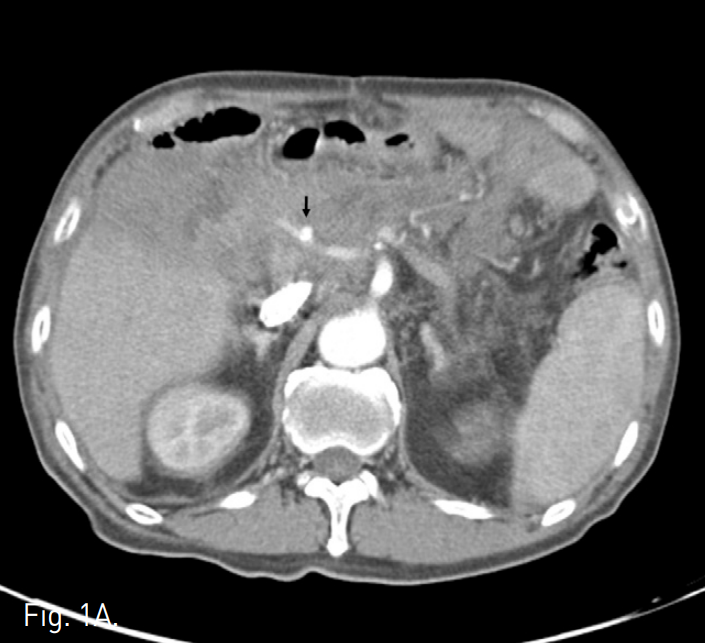

CT상 총간동맥에 약 0.6cm 크기의 가성동맥류가 있고 그 주변으로 혈종이 관찰되었다(Fig. 1A). 간동맥 조영술에 서 총간동맥에 pseudoa neurysmal sac과 인접한 부위의 spasm, 그리고 가성동맥류 주변으로 조영제의 누출이 확인되었다(Fig. 1B).

A. Abdominal CT shows a small pseudoaneurysm of the common hepatic artery (arrow) with surrounding hematoma.